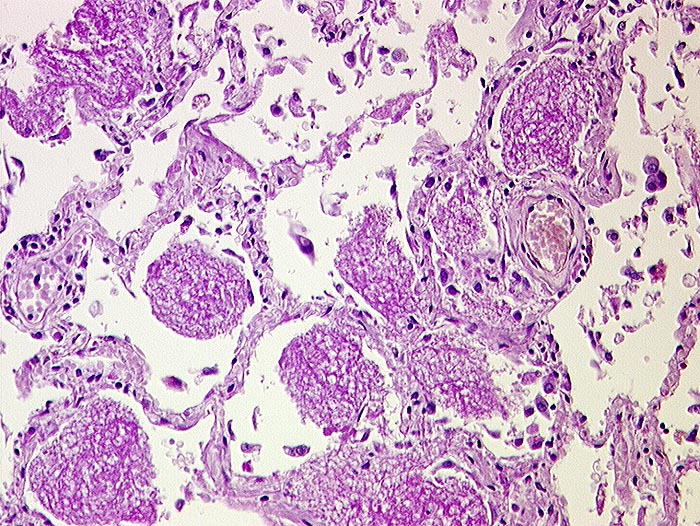

Pneumocystis carinii

Bei Pneumocystis carinii handelt es sich um eine Pilzinfektion. Die Organismen sind in intraalveolärem schaumigem Material nachweisbar. Dieses flockig-schaumige Material färbt sich in der Papanicolaou Färbung eosinophil oder basophil. Die Erreger selbst sind in der Papanicolaou Färbung nur schlecht sichtbar. Die Zysten lassen sich aber mit der Grocott-Versilberung darstellen. Sie sind 4 bis 8 Mikrometer gross, rundoval und enthalten einen zentralen schwarzen Punkt. Die Zysten enthalten bis zu acht 0.5 bis 1 Mikrometer messende Trophozoiten.